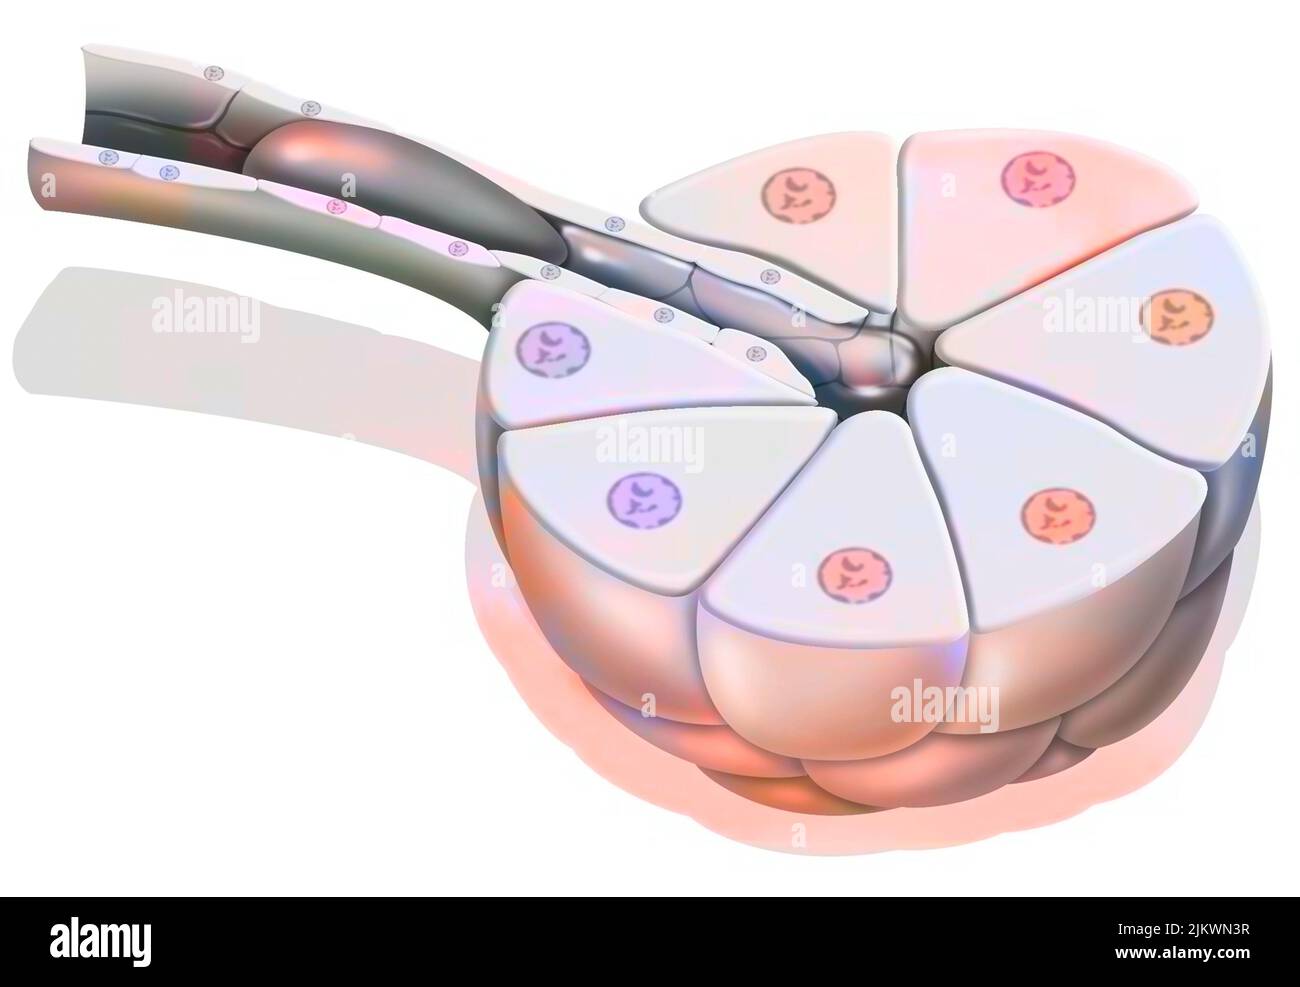

RF2JKWTKH–Canal ionique dépendant du ligand : l'attachement d'une molécule particulière provoque l'ouverture du canal.